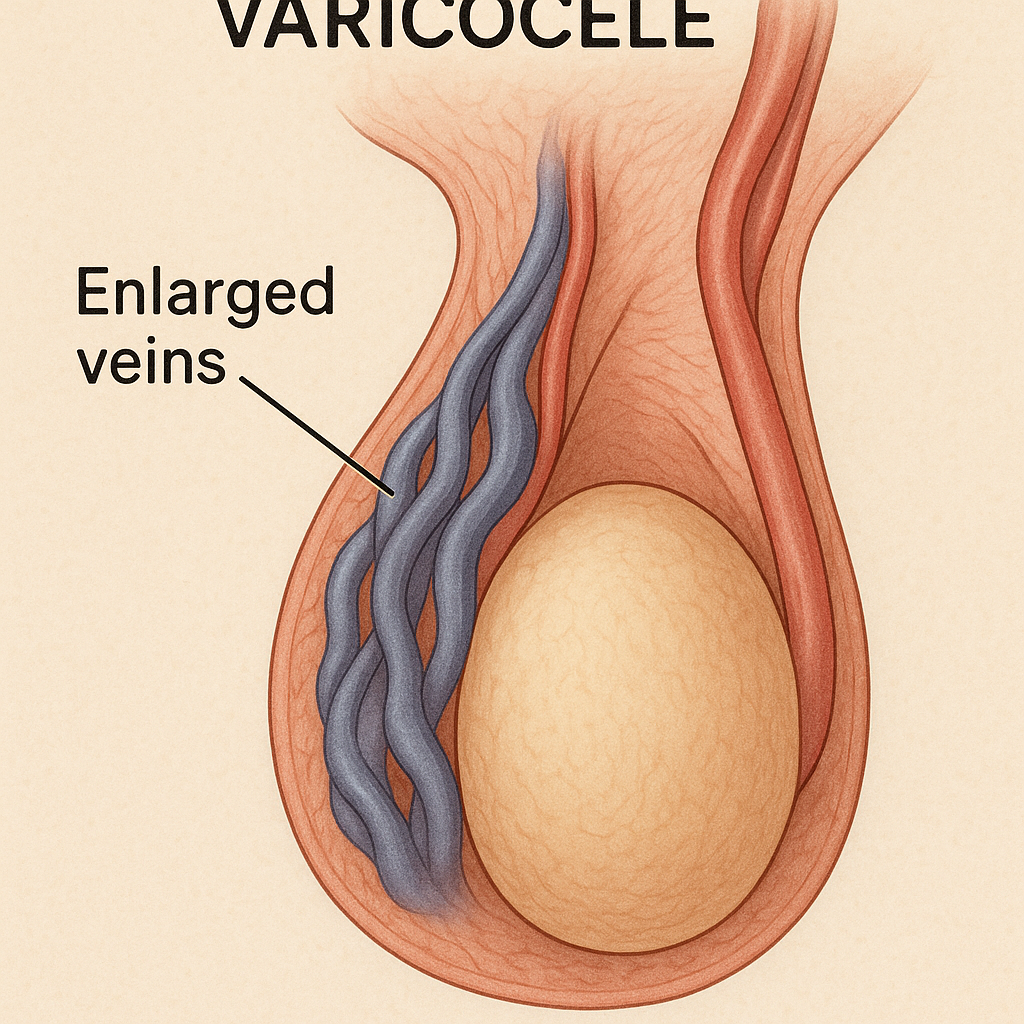

# Male